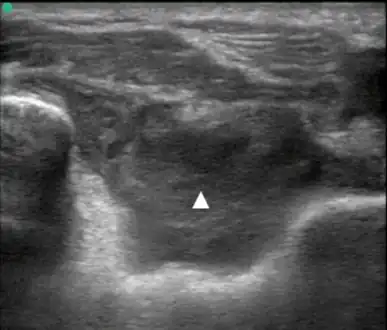

| Lipohemarthrosis (blood and fat in the joint space) seen in a person with a subtle tibial plateau fracture. The arrow indicates a fluid level between the upper fat component and the lower blood component. | |